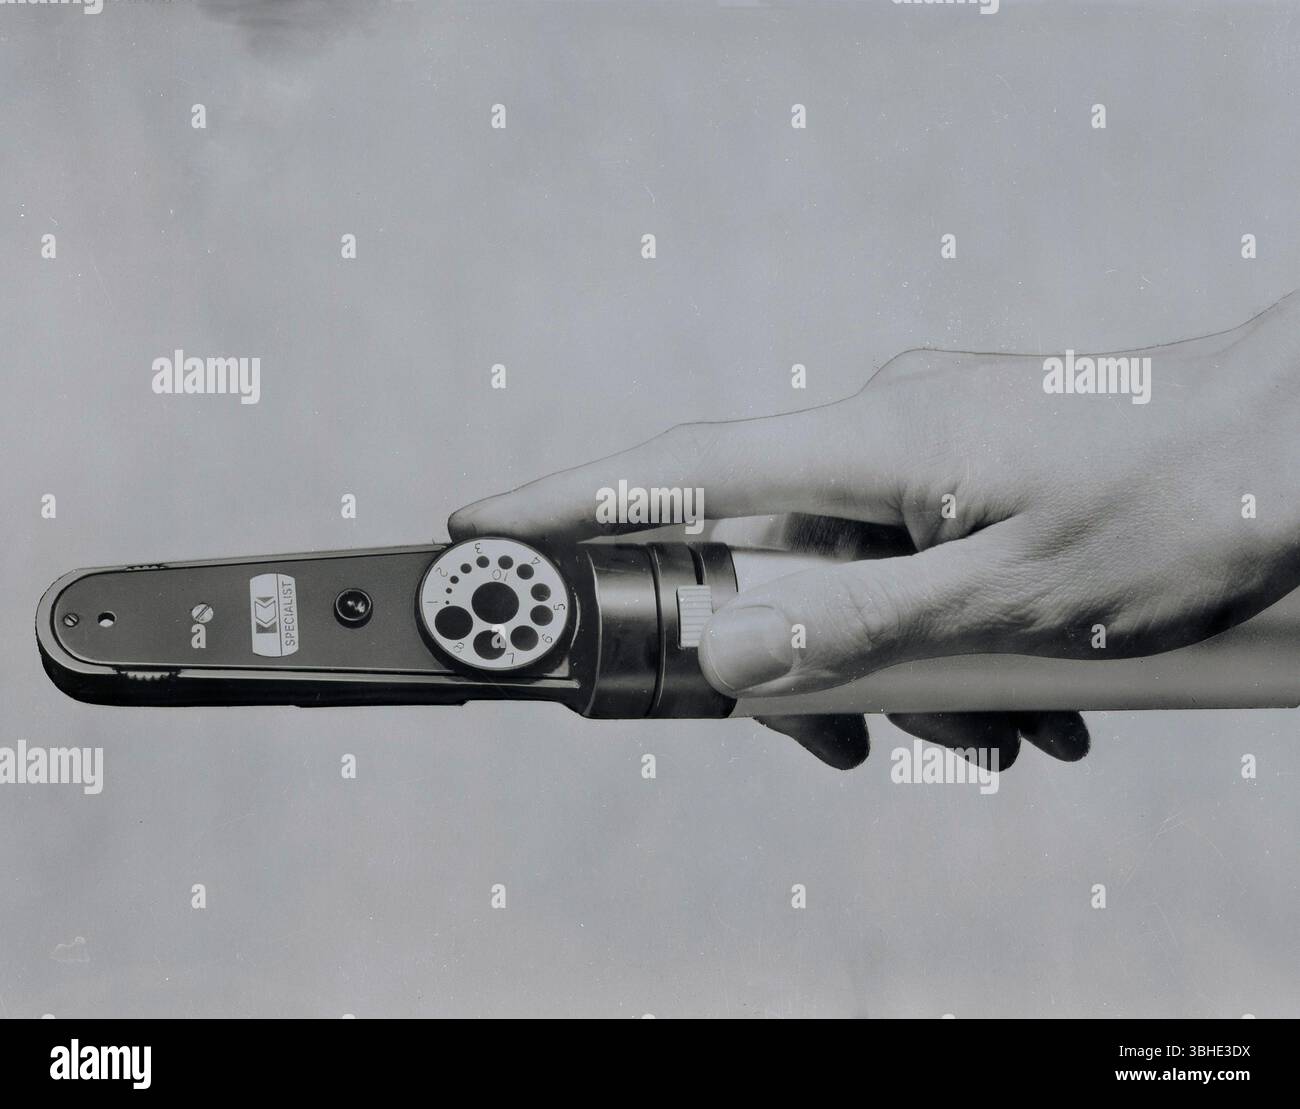

1950s, historical, a Keeler specialist opthalmoscope used in Ophthalmoscopy. Also called funduscopy, it is a method whereby a practitioner is able to see inside the fundus of the eye and other structures using an ophthalmoscope (or funduscope). Undertaken as part of an eye examination. The ophthalmoscope can also be used as part of a routine physical examination. Stock Photohttps://www.alamy.com/image-license-details/?v=1https://www.alamy.com/1950s-historical-a-keeler-specialist-opthalmoscope-used-in-ophthalmoscopy-also-called-funduscopy-it-is-a-method-whereby-a-practitioner-is-able-to-see-inside-the-fundus-of-the-eye-and-other-structures-using-an-ophthalmoscope-or-funduscope-undertaken-as-part-of-an-eye-examination-the-ophthalmoscope-can-also-be-used-as-part-of-a-routine-physical-examination-image681963574.html

1950s, historical, a Keeler specialist opthalmoscope used in Ophthalmoscopy. Also called funduscopy, it is a method whereby a practitioner is able to see inside the fundus of the eye and other structures using an ophthalmoscope (or funduscope). Undertaken as part of an eye examination. The ophthalmoscope can also be used as part of a routine physical examination. Stock Photohttps://www.alamy.com/image-license-details/?v=1https://www.alamy.com/1950s-historical-a-keeler-specialist-opthalmoscope-used-in-ophthalmoscopy-also-called-funduscopy-it-is-a-method-whereby-a-practitioner-is-able-to-see-inside-the-fundus-of-the-eye-and-other-structures-using-an-ophthalmoscope-or-funduscope-undertaken-as-part-of-an-eye-examination-the-ophthalmoscope-can-also-be-used-as-part-of-a-routine-physical-examination-image681963574.htmlRM3BHE3DX–1950s, historical, a Keeler specialist opthalmoscope used in Ophthalmoscopy. Also called funduscopy, it is a method whereby a practitioner is able to see inside the fundus of the eye and other structures using an ophthalmoscope (or funduscope). Undertaken as part of an eye examination. The ophthalmoscope can also be used as part of a routine physical examination.